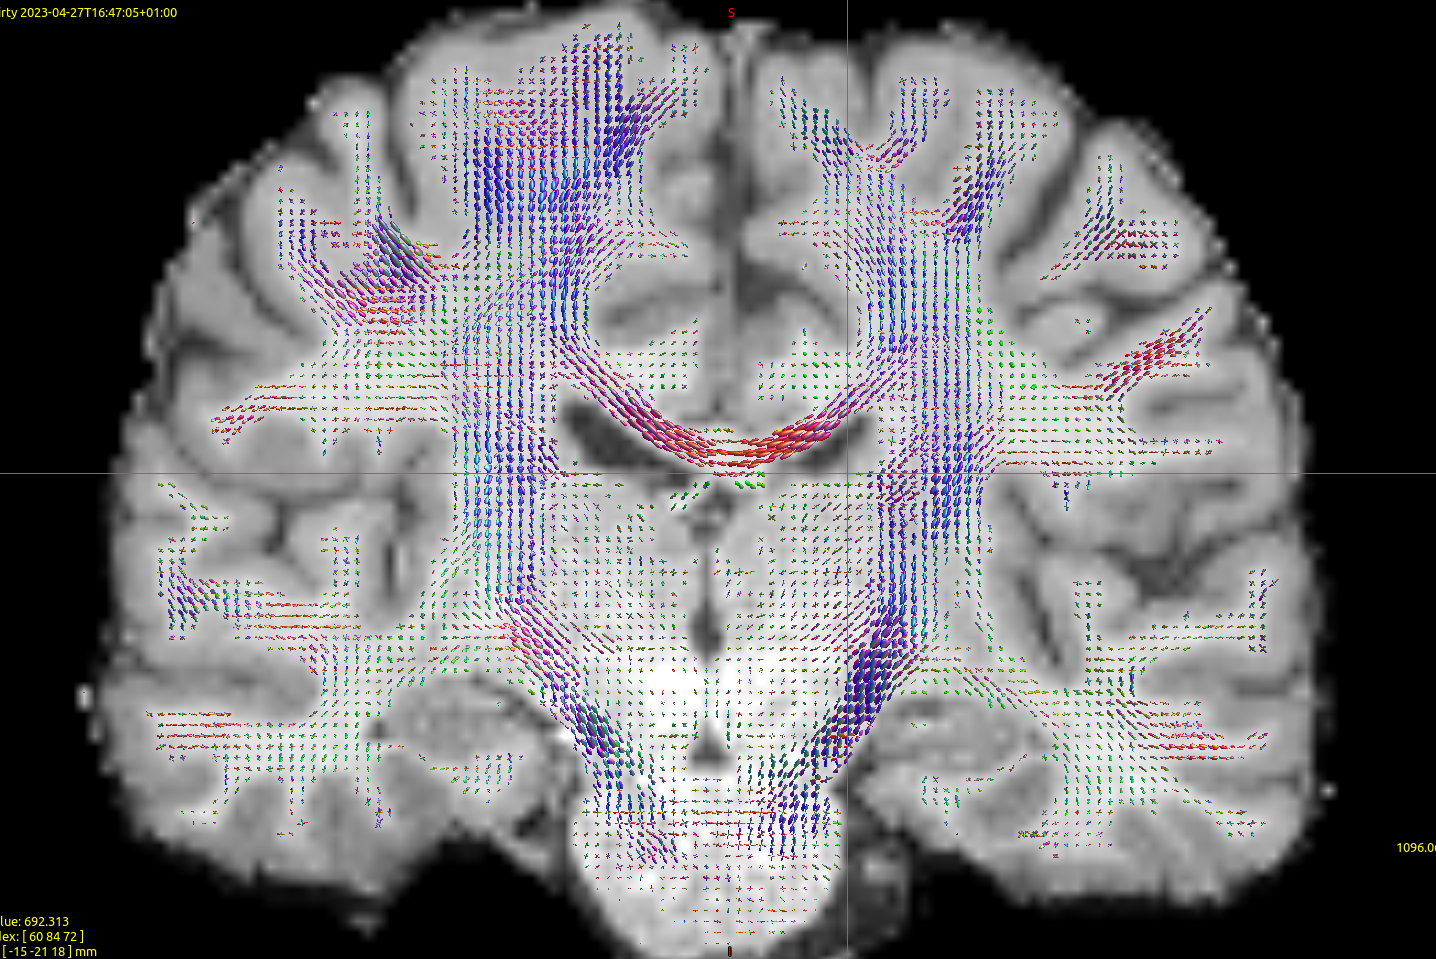

In order to do some sanity check I have turned to HCP data; I have selected the b1000 shell, computed the response function using the Tournier method,

which leads to seemingly OK FOD data:

Using iFOD2 here as well, this time with

seed_count=100000

step_size=0.7

min_length=50

max_length=340

and seeding the entire WM. Note that I changed the min length here to try to see if that is a problem for the high res data/see if I get better results for HCP. Changing the cutoff down to 0.04 improves results only a tiny bit, but overall I still get poor results for the cerebellar region (below). The first thing that strikes me is that the MCP is unable to properly contour the pons: